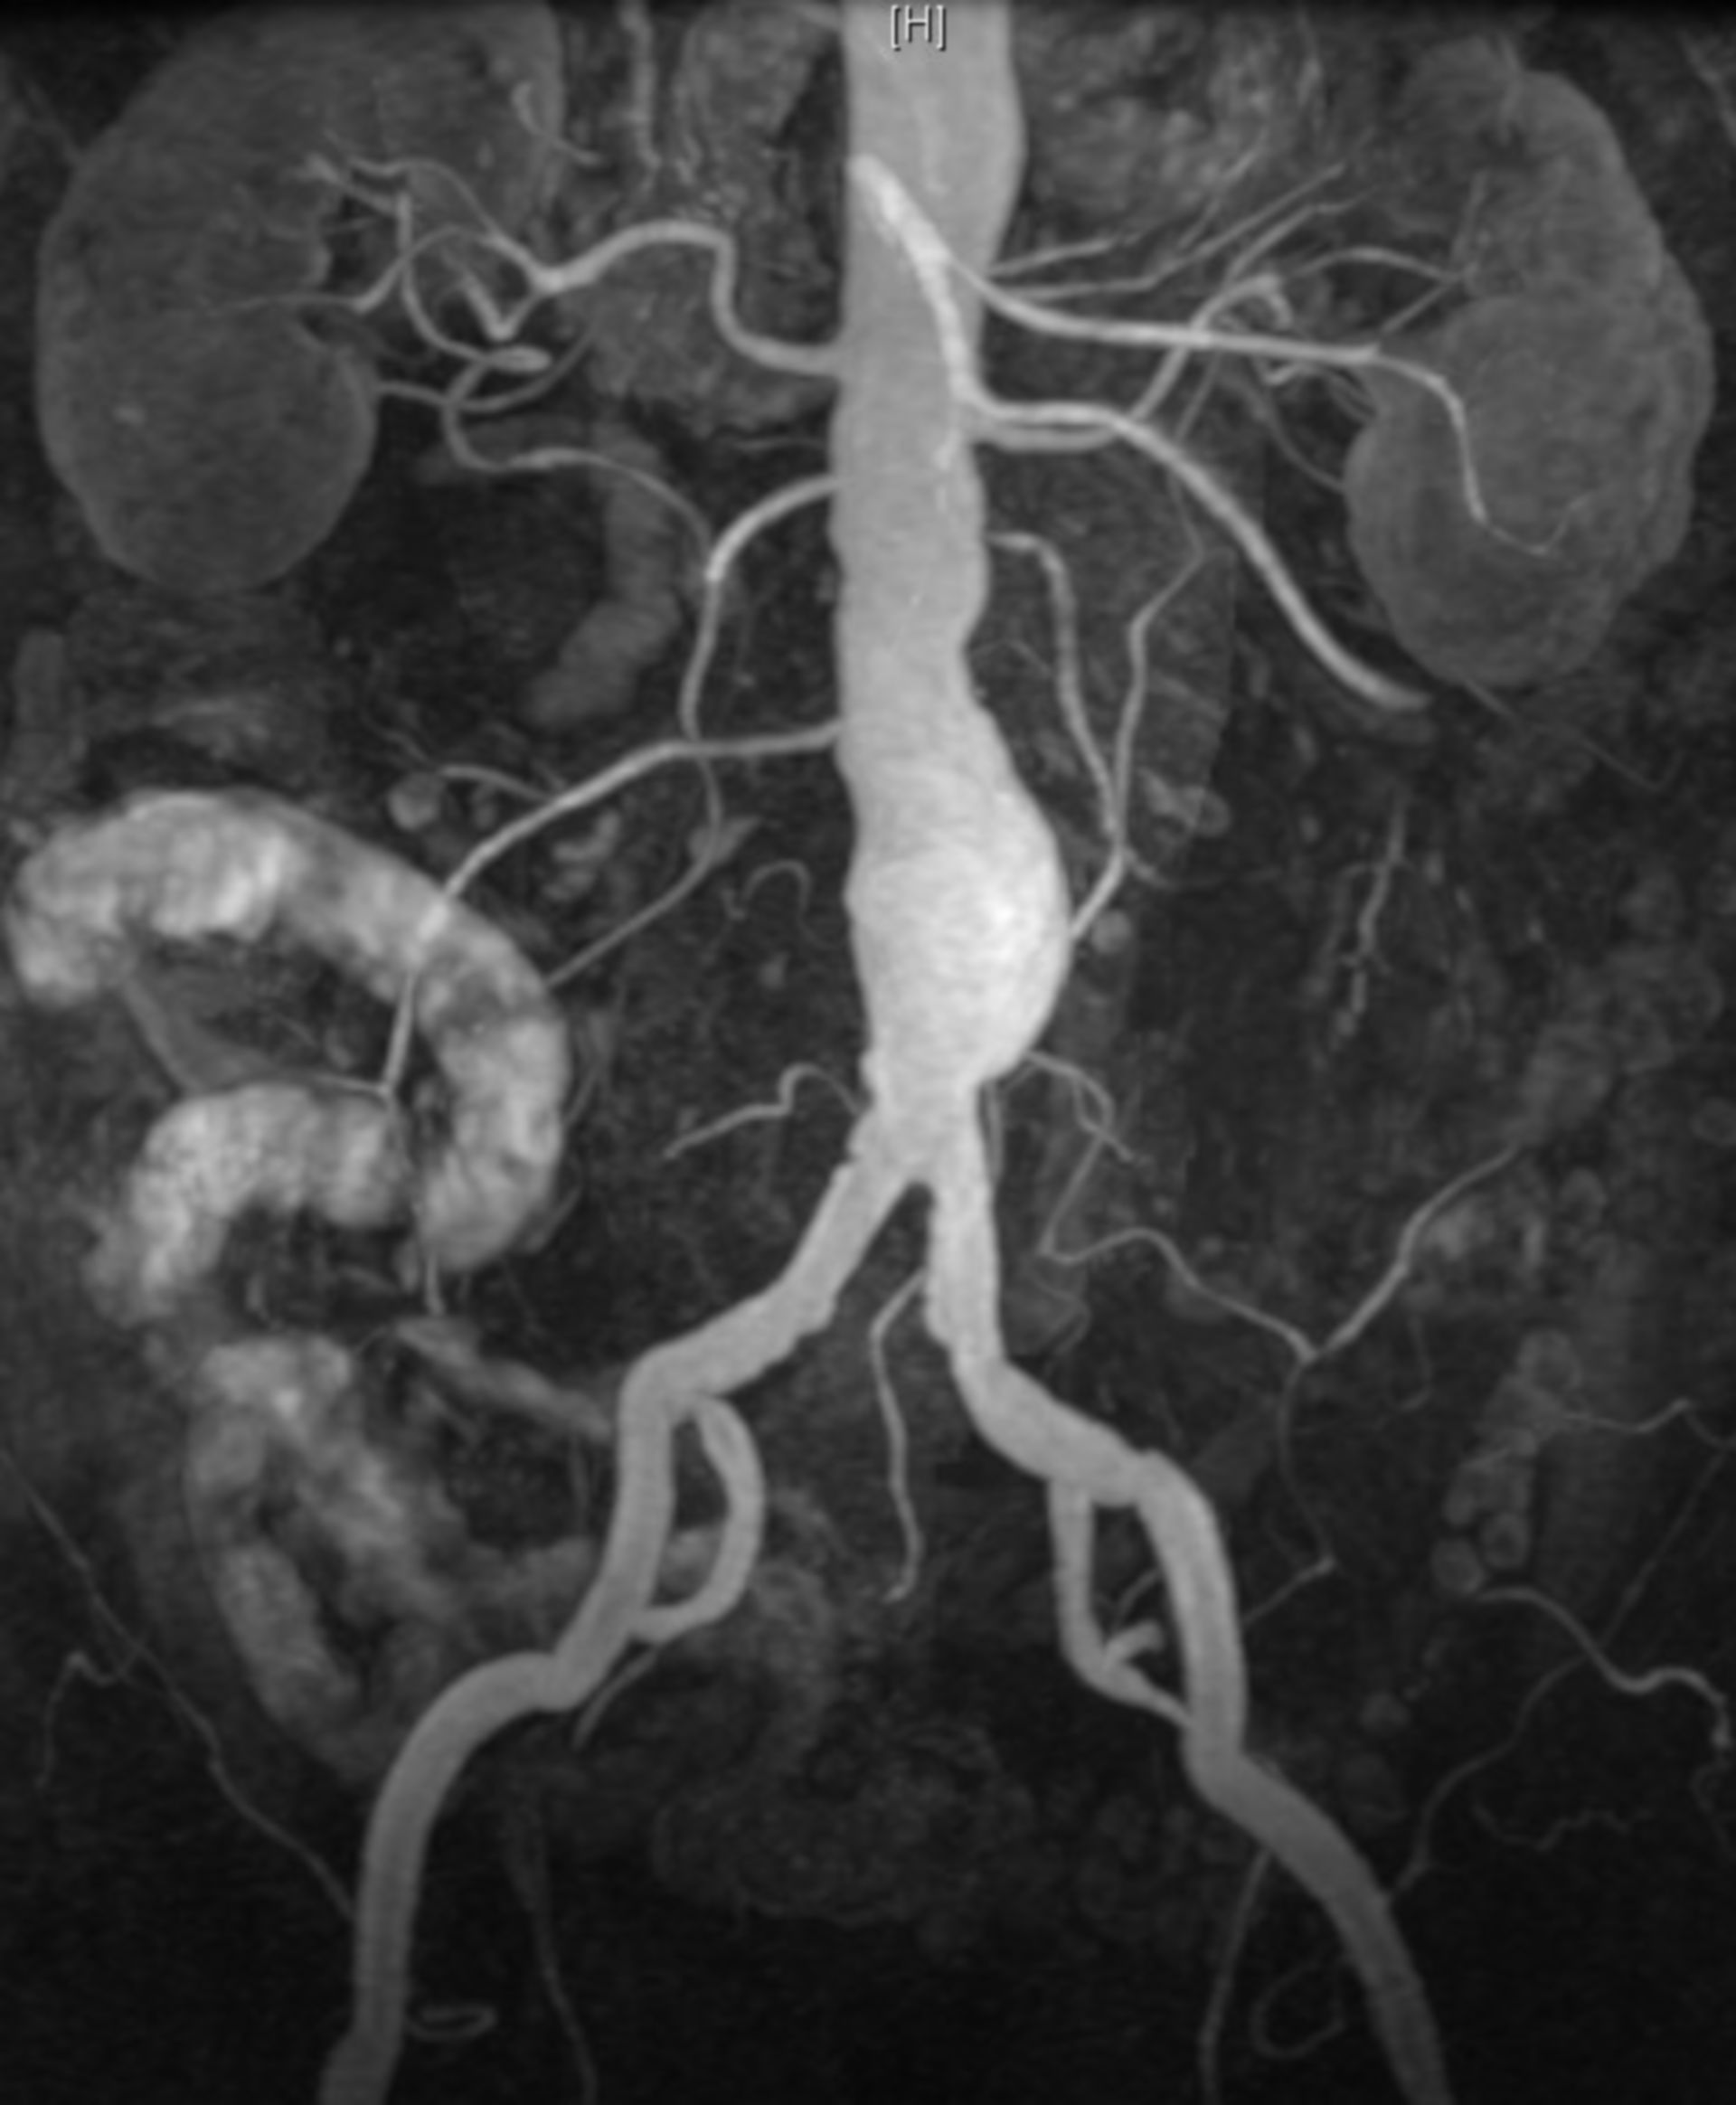

http://www.ncbi.nlm.nih.gov/pubmed/2625160?tool=bestpractice.com [Figure caption and citation for the preceding image starts]: Результат ультразвукового исследования аневризмы брюшной аорты размером 3,8 х 4,2 смМичиганский университет, в частности, клинические случаи из практики врача Упчурч, представляющие работу отделений сосудистой хирургии и радиологии [Citation ends].